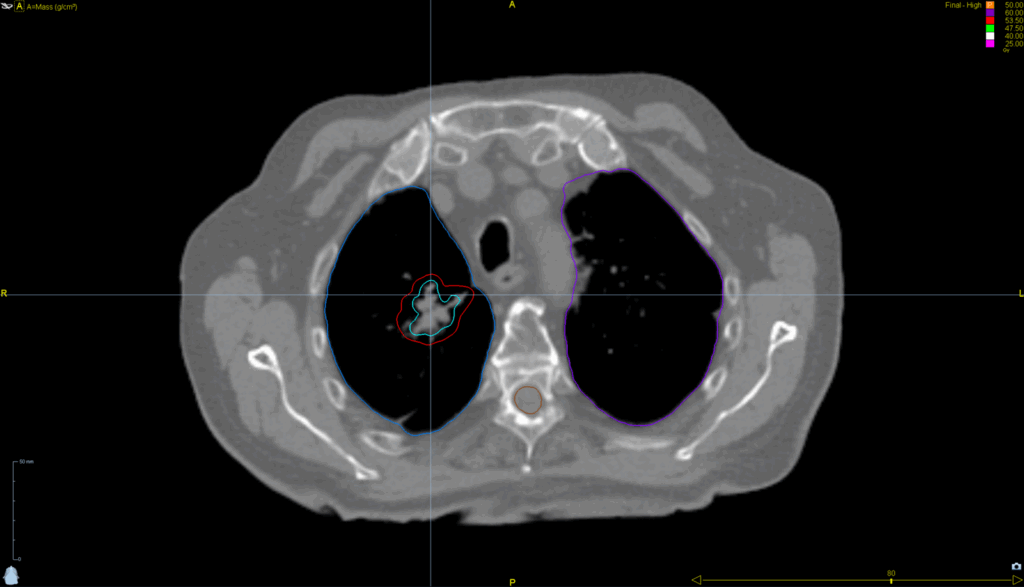

Lung SBRT with Synchrony® Fiducial Tracking™ and Respiratory Modeling

< View All Plan Studies RADIXACT SYSTEM Lung SBRT with Synchrony® Fiducial Tracking™ and Respiratory Modeling Case History AGE: 76-year-oldGENDER: Male Medical History Immidiate tolerance: Grade II dermatitis with eyelid edema, Grade I conjunctivitis resolved with Sterdex Diagnosis: Squamous cell carcinoma of the right lower eyelid Planning CT Images Treatment Plan Images ClearRT® Images Treatment […]